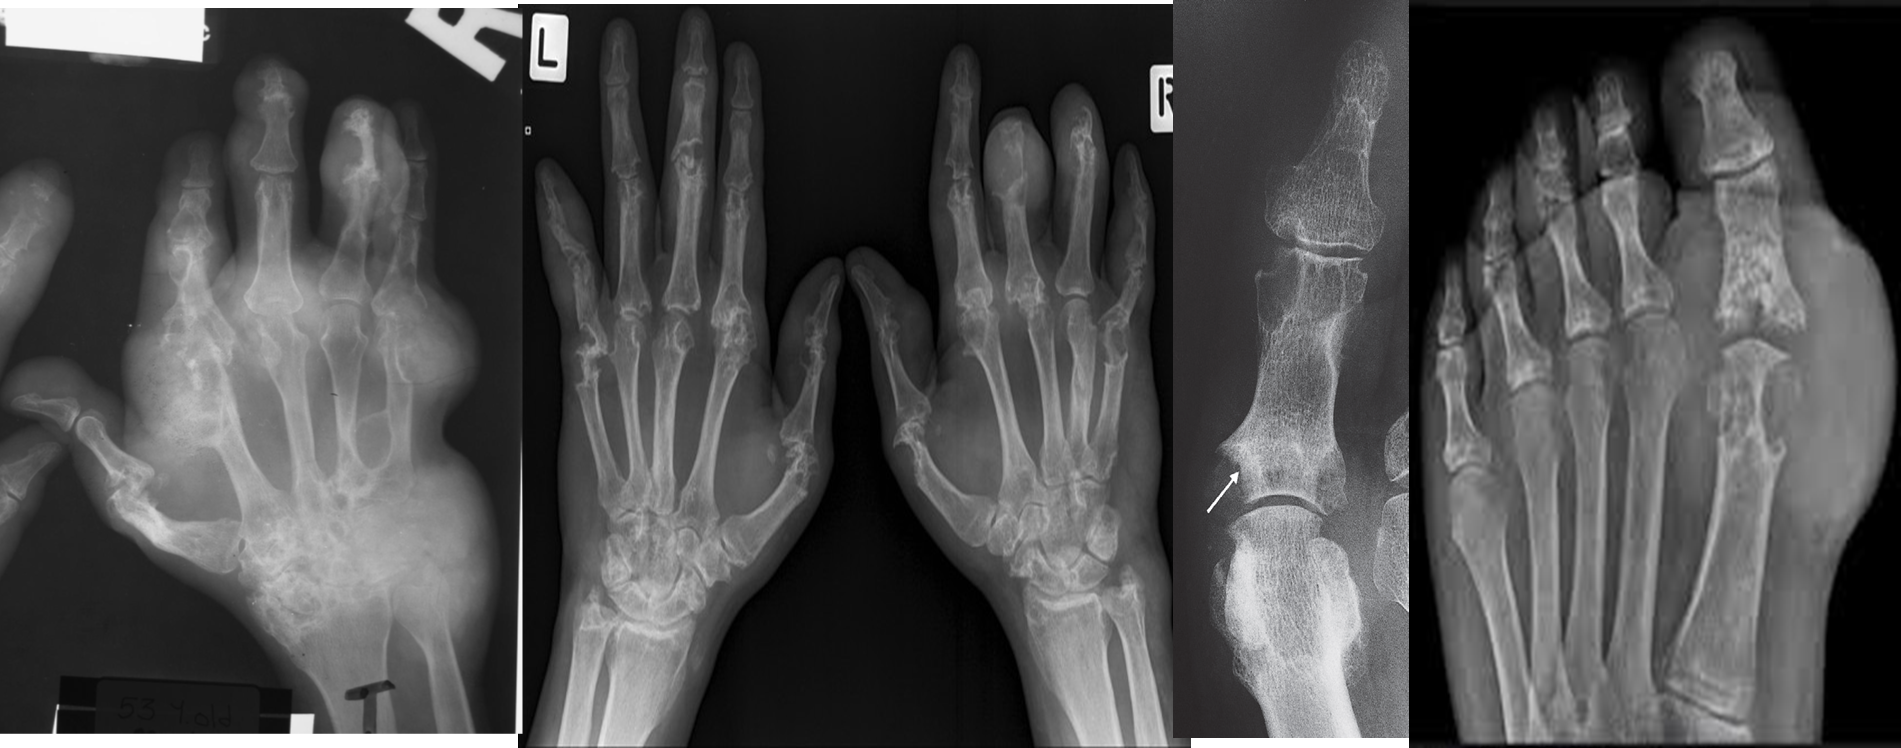

• Erosions. Malalignment.

• Around the erosion there is a swelling “ Rounded soft tissue enlargement” TOPHUS

• The earliest change is soft tissue swelling. At a later stage, erosions occur that, unlike rheumatoid arthritis. These erosions have a well-defined, often sclerotic, edge and frequently have overhanging edges Gout characteristically involves the metatarsophalangeal joint of the big toe.

Erosion: there is a typical well-defined erosion with an overhanging